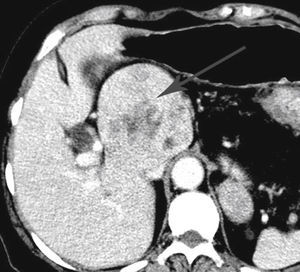

Caso clínicoPaciente femenina de 74 años de edad, diabética de 11 años de evolución, en tratamiento con hipoglucemiantes por vía oral, con lesión ocupante en el lóbulo caudado hepático de 8cm en diámetro mayor, diagnosticada mediante tomografía computada (fig. 2), sin datos clínicos o bioquímicos de cirrosis hepática (ascitis y encefalopatía ausente, albúmina 4.1g/ dl, bilirrubina total 1.4mg/dl, tiempo de protrombina 10.9, INR 0.93, plaquetas 228 × 103 cél/mm3) y alfafetoproteína sérica 3.7 UI/l. Sus serologías hepáticas contra hepatitis A, B y C fueron negativas. Sometida a laparotomía exploradora por abordaje subcostal bilateral con ultrasonido transoperatorio, sin encontrar otras lesiones hepáticas. Se efectuó una resección completa de la lesión, con un tiempo quirúrgico de 270min, utilizando fractura digital y hemostasia mediante pinzas de Kelly, con maniobra de Pringle por 13min, con movilización hepática completa para exposición de la vena cava inferior infrahepática previo a la movilización del tumor de lóbulo caudado, exposición de las venas hepáticas que tributan directamente a la superficie anterior de la vena cava inferior para su ligadura, mediante retracción anterior hepática, y drenaje de succión cerrada al lecho quirúrgico. El sangrado transoperatorio fue de 3,000ml y se transfundieron 7 paquetes globulares (figs. 3 y 4). Evolución postoperatoria satisfactoria y alta al décimo día posquirúrgico. La lesión tiene aspecto histológico de hepatocarcinoma moderadamente diferenciado con patrón sólido (hematoxilina y eosina, 5×), y las células neoplásicas son grandes, poligonales con núcleos pleomórficos, con nucléolos, multinucleación y mitosis tetra-polares (hematoxilina y eosina, 40×) (fig. 5 A y B). Se obtuvo un margen negativo de 4mm.